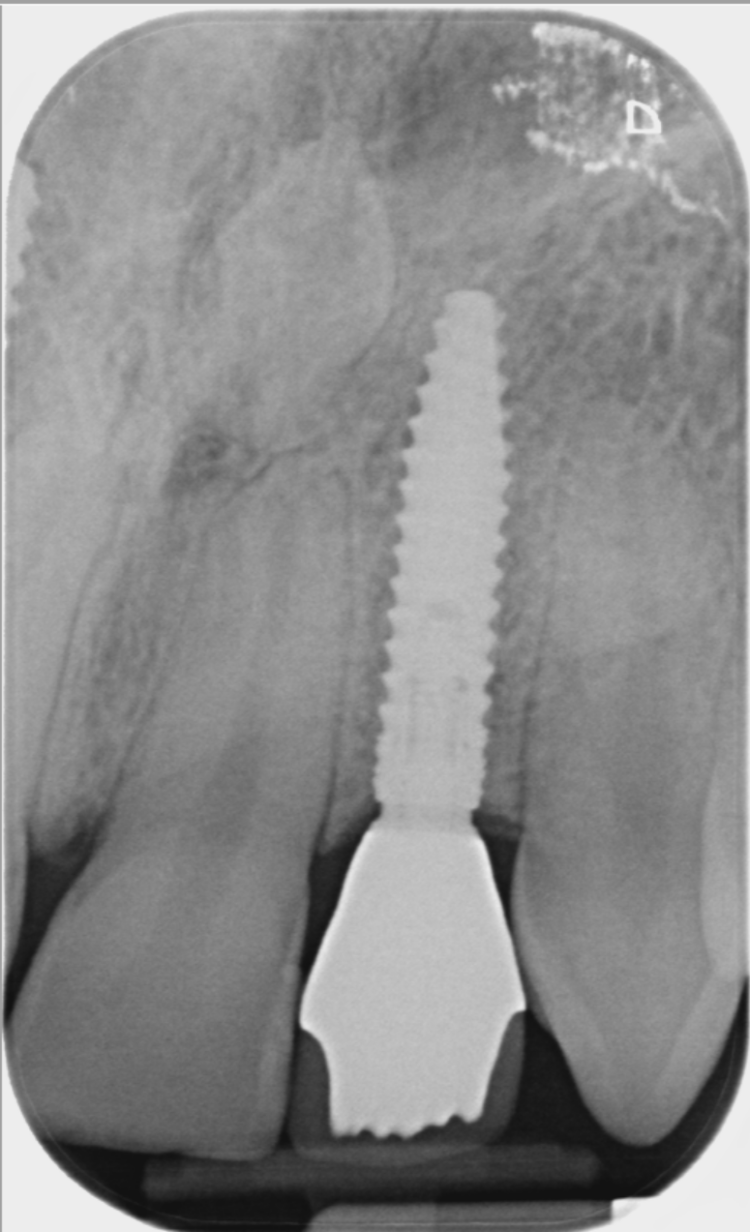

The implant surgery was performed in May 2023 and was filmed live as part of a surgical demonstration for the delegates on a guided surgery course being run by the Fitz Fahey Academy. Implants were placed in the UR2 and UL2 spaces with simultaneous hard and soft tissue grafting. Following the surgery, the patient was provided temporary teeth and instructed to avoid putting undue pressure on the implants during healing.

A week after the surgery, the patient was seen for a healing review, during which X-rays were taken and sutures were removed. After sufficient healing, the patient returned for an impression appointment, where the temporary teeth were removed and scans were taken to fabricate the final crowns.